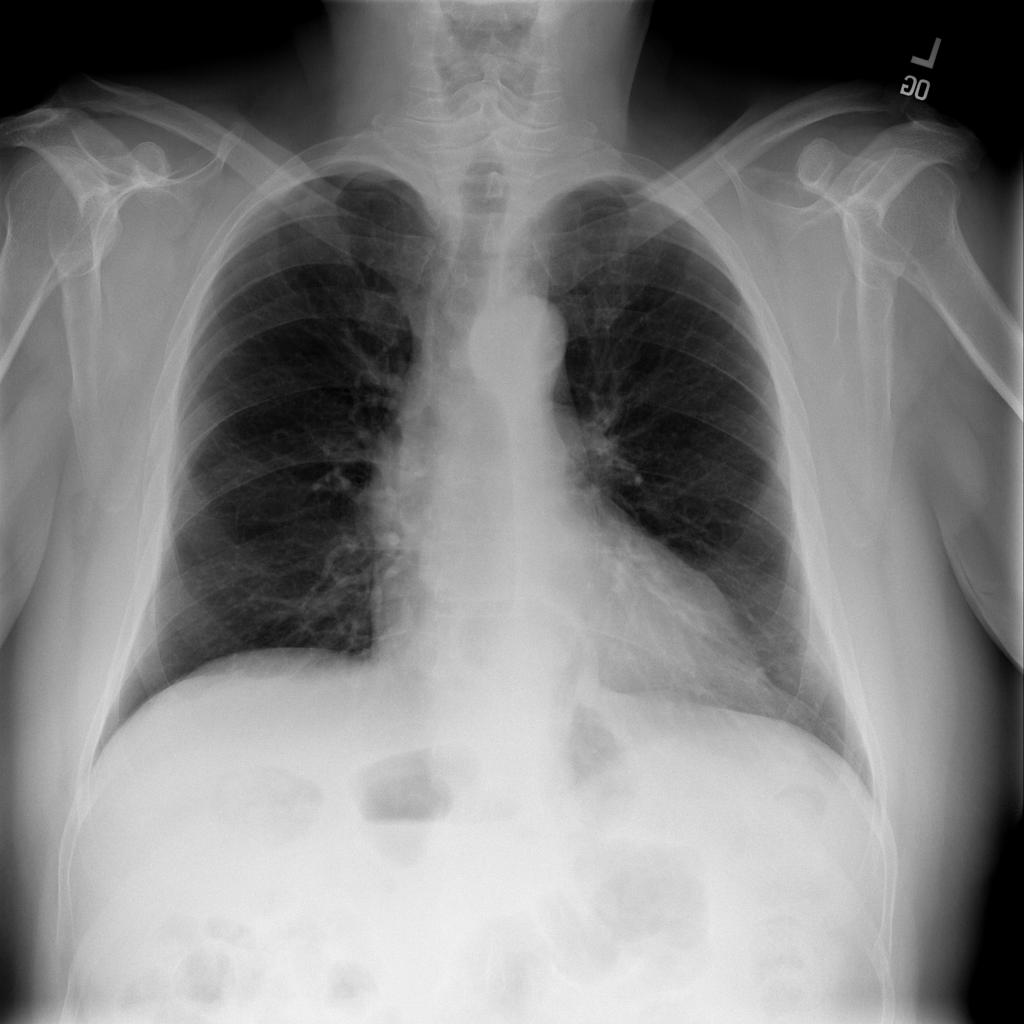

Showing up to 90 reference images for Hernia.

PAT-C048 · IMG-000Hernia

PAT-C048 · IMG-000

PA